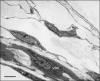

The pulmonary vasculature comprises three anatomic compartments connected in series: the arterial tree, an extensive capillary bed, and the venular tree. Although, in general, this vasculature is thin-walled, structure is nonetheless complex. Contributions to structure (and thus potentially to function) from cells other than endothelial and smooth muscle cells as well as those from the extracellular matrix should be considered. This review is multifaceted, bringing together information regarding (i) classification of pulmonary vessels, (ii) branching geometry in the pulmonary vascular tree, (iii) a quantitative view of structure based on morphometry of the vascular wall, (iv) the relationship of nerves, a variety of interstitial cells, matrix proteins, and striated myocytes to smooth muscle and endothelium in the vascular wall, (v) heterogeneity within cell populations and between vascular compartments, (vi) homo- and heterotypic cell-cell junctional complexes, and (vii) the relation of the pulmonary vasculature to that of airways. These issues for pulmonary vascular structure are compared, when data is available, across species from human to mouse and shrew. Data from studies utilizing vascular casting, light and electron microscopy, as well as models developed from those data, are discussed. Finally, the need for rigorous quantitative approaches to study of vascular structure in lung is highlighted.